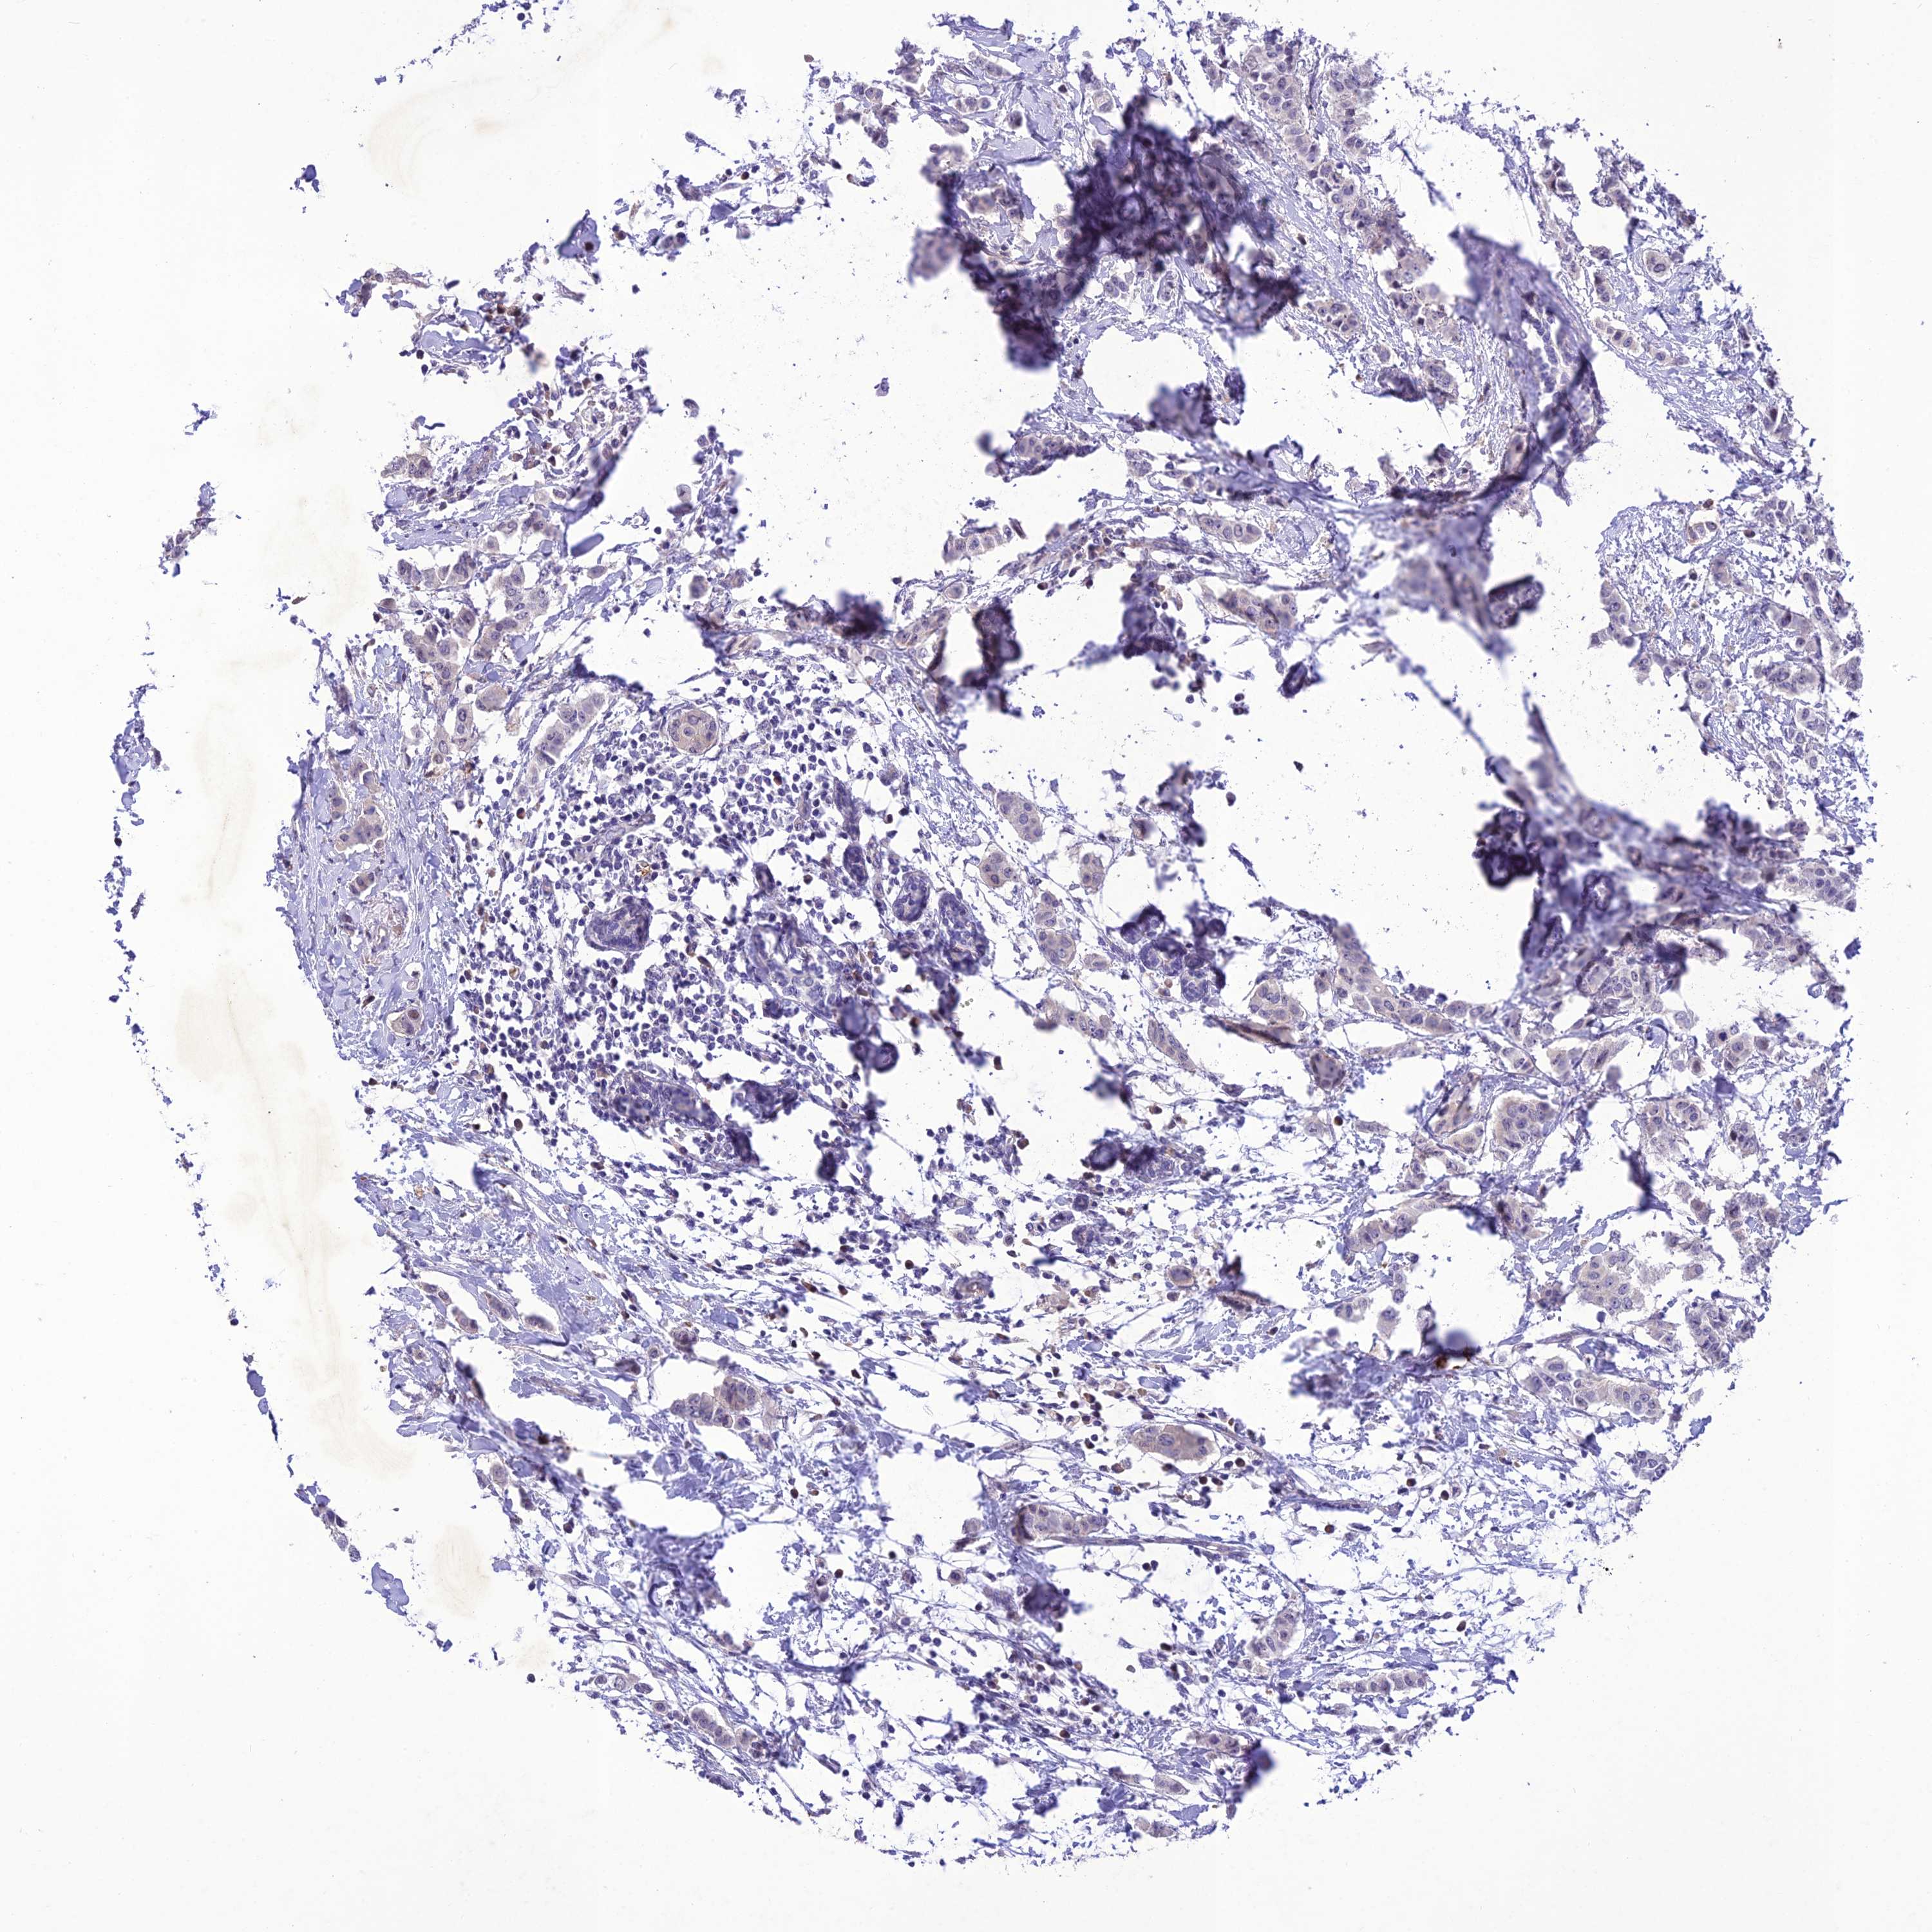

CANCER BREAST CANCER Show tissue menu

BRCA TCGA BRCA VALIDATION PROTEIN EXPRESSION